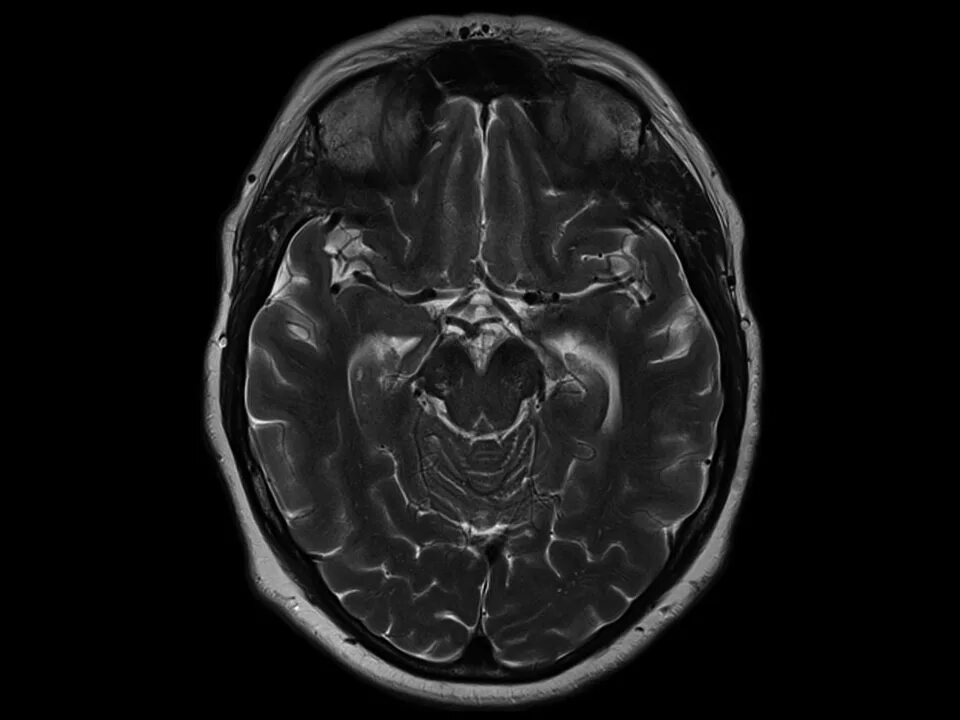

После мрт головного мозга